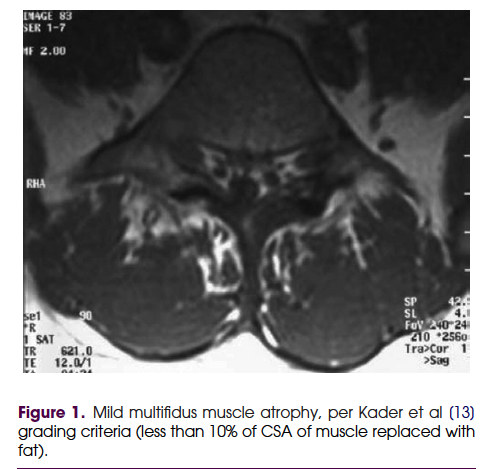

만성요통에서 다열근의 역할에 관한 review논문